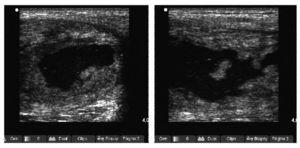

El estudio ecográfico mostró de nuevo colección anecoica de 5 × 10 (fig. 2) y la imagen de RM puso de manifiesto una colección purulenta en el tercio proximal de tensor del músculo de la fascia lata (fig. 3).

Figura 2 Imagen anecoica de bordes bien delimitados compatible con absceso muscular en el tensor de la fascia lata.